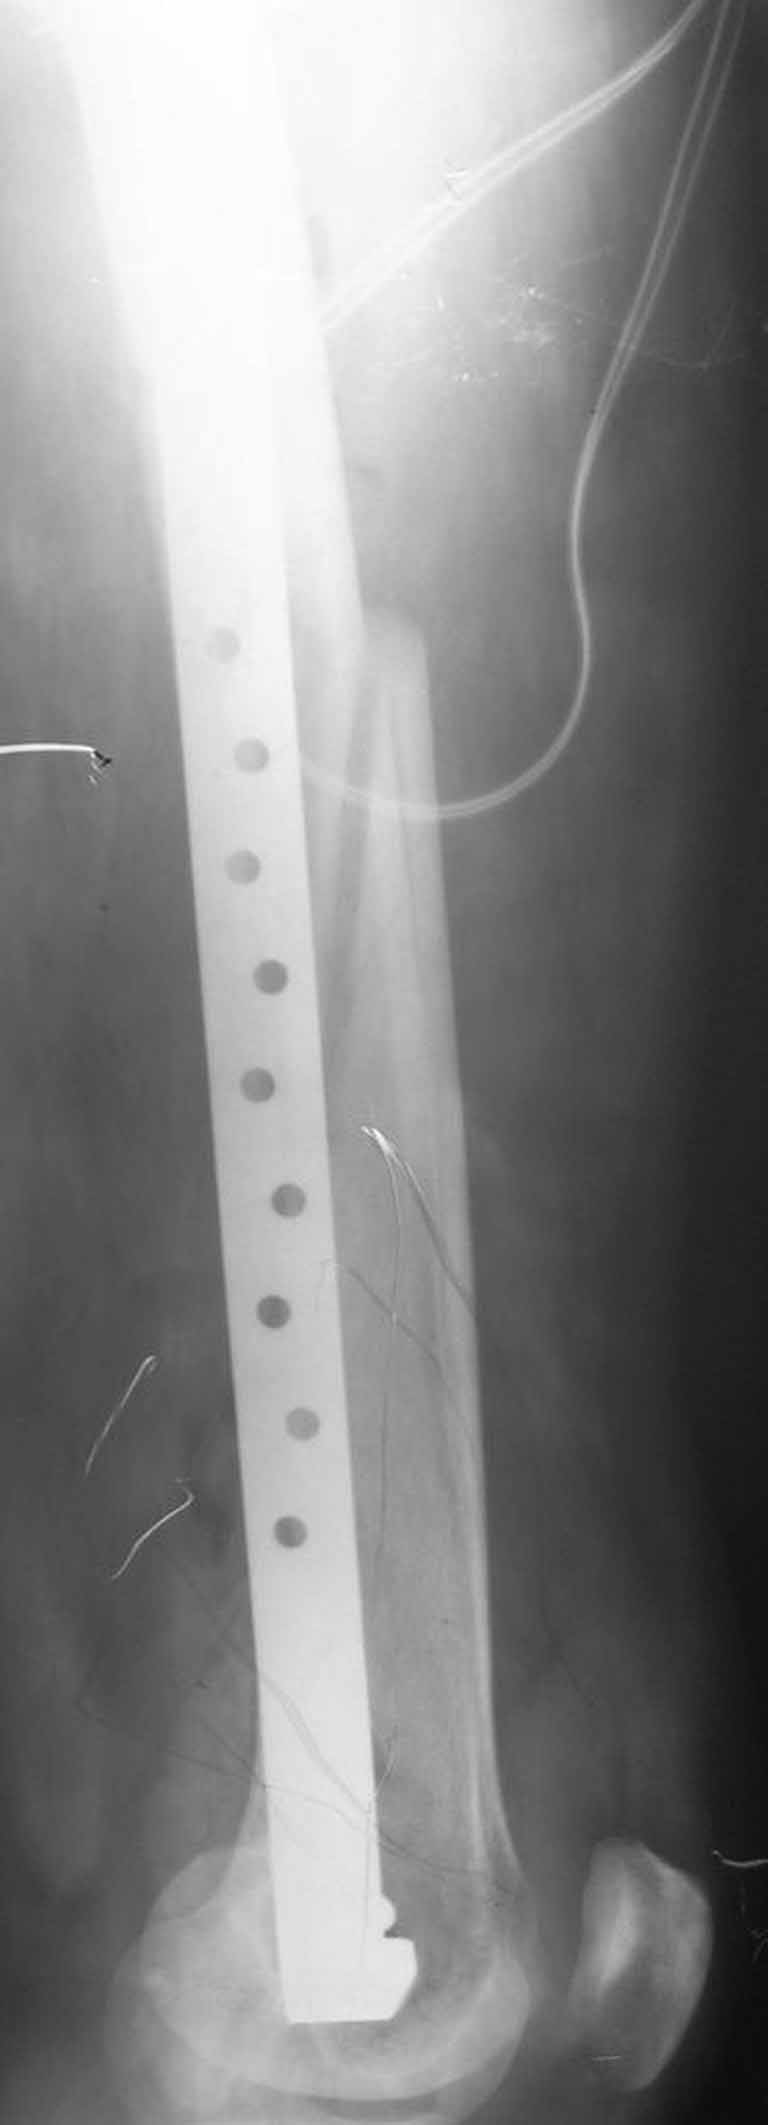

Представляю вам один из наших недавних случаев выполнения малоинвазивного остеосинтеза бедренной кости обычной пластиной 95 градусов. Длина восстановлена с помощью дистрактора (по сути это основная и б(о)льшая часть репозиции). Произведено два небольших доступа, проведена спица направитель. Рентген-контроль для подтверждения достаточной длины/оси (ЭОП использовался в другой операционной). Создание туннеля обратной стороной фиксатора. Поворот фиксатора, введение клинка по спице. Фиксация проксимального и дистального концов пластины.